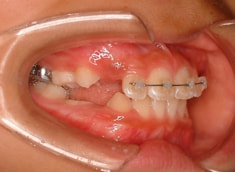

治療法:上顎拡大装置+フルパッシブブラケット(クリアスナップ)+フェイスマスク等

治療期間:12ヶ月

治療開始後3ヶ月で、すでに前歯がジャンプしていますが、ここで注意が必要です。これは前歯の傾斜で反対咬合が一時的に解消しているだけです。ここからしっかりとフェイスマスクを使用し、上顎の牽引をしなくてはいけません。

ジャンプしただけでは「治った」ことにはなりません。今後身長と一緒に伸びてくる下顎の成長に備える必要があります。

外科矯正も回避できて、さらに非抜歯で本格矯正を行うことができると診断し、現在2期治療中です。